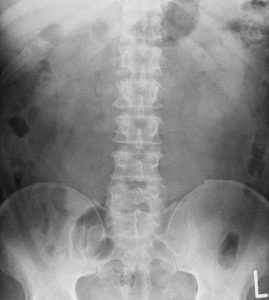

- 整形外科:レントゲン、MRI → 骨や椎間板の問題を探す

実は、腰痛全体の約85%は「非特異的腰痛」と呼ばれています。

これは「画像検査では異常が見つからないが、痛みがある」という状態。

- 骨には問題ない

- 椎間板も大丈夫

- 神経の圧迫もない

それでも痛い。

- 腰痛のない人の60〜80%にも、MRIで椎間板の異常が見られる

- 逆に、椎間板ヘルニアがあっても痛みを感じない人もいる